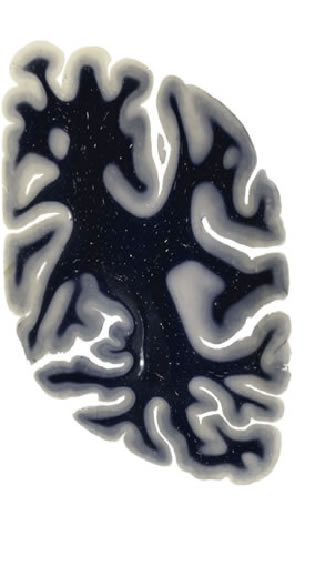

Hi-Resolution Sections · Cells (Nissl Staining) · Virtual Microscopy

Frontal sections (Nissl) from the Atlas Brain:

Macroscopy

Slice ID:

r4-0720

Plate NR:

57

Position:

56,2 mm